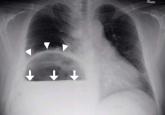

Article‘Air-raising’: An air-fluid level in the right subphrenic regionAuthor:Anupam Gupta, MDPublish date: September 1, 2016Plain chest radiography showed dramatic elevation of the right hemidiaphragm with a large subphrenic air-fluid level.Read More